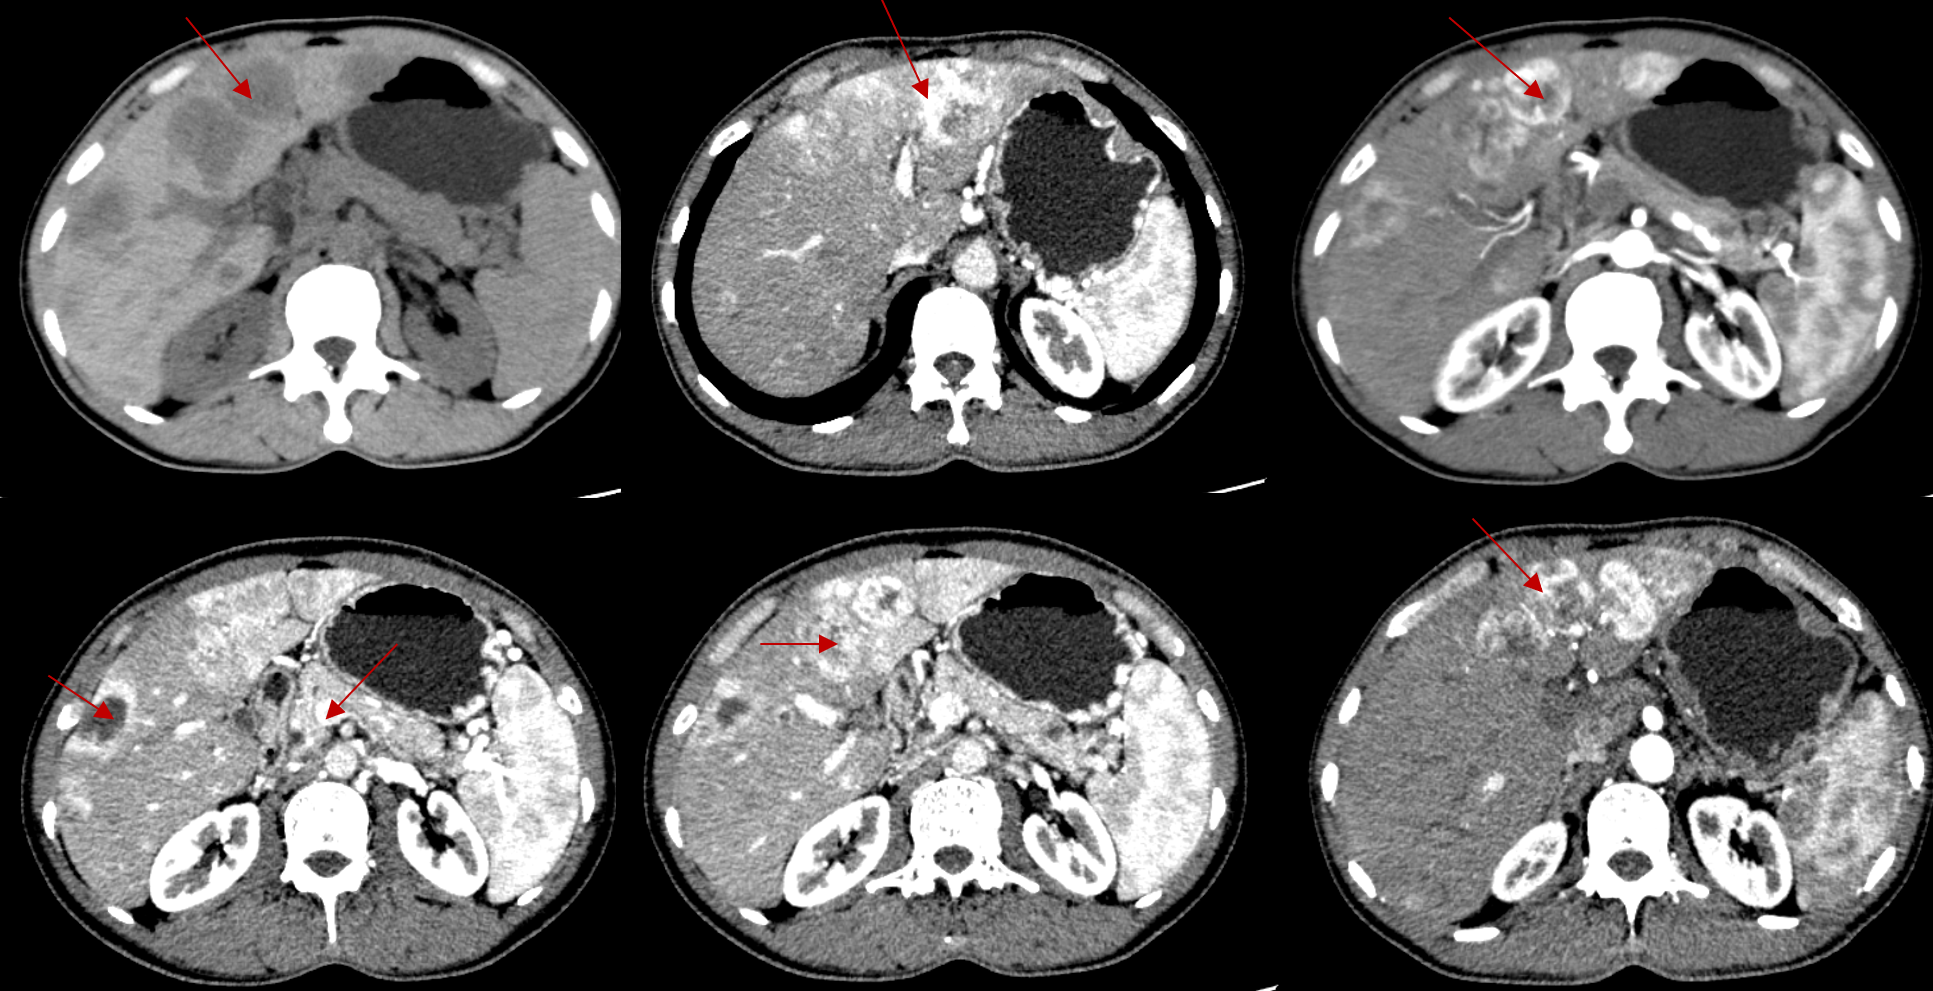

首次入院CT评估:影像所见:肝脏多发低密度结节、肿块,大者长径约4.8cm(S5),边界大致清楚,部分融合,胰腺平扫大小、形态及密度正常;诊断意见:1、肝脏多发结节、肿块,多考虑恶性,神经内分泌性肿瘤可能,转移与原发待鉴别。

患者于2024-09-02第1次行“经肝动脉DSA+TAE经肠系膜上动脉DSA术”,手术经过顺利,术后予保肝等对症支持治疗,评估病情后有奥曲肽治疗指征,于2024-09-03行“奥曲肽”治疗:奥曲肽微球:40mg d1 q4w,治疗期间予抑酸护胃、保肝等处理。1周期内分泌治疗后复查(2024-10-12)示:1、肝脏多发结节、肿块,部分较前缩小,建议结合临床复查。2、胰尾部结节,建议结合MRI或复查。胃周静脉曲张,腹主动脉壁多发钙斑,上中腹膜后未见肿大淋巴结。由于治疗有效,患者于2024-10-16行第2次“经肝动脉DSA+TAE,经肠系膜上动脉DSA+TAE术”,2024-10-19行第2周期“醋酸奥曲肽微球”治疗(醋酸奥曲肽微球40mg d1 Q4W)。

2024-11-04患者于他院行PET-CT(68Ga+18F)检查,结果显示:1. 约胰尾病变可符合神经内分泌肿瘤改变,并伴肝脏多发转移。2. 双肺结节倾向炎性病灶。3. 慢性膀胱炎可能。4. 右上颌窦炎。3周期内分泌治疗后复查(2024-11-29)显示PR。基于此,患者于2024-12-03行第3次“经肝动脉DSA+TAE,经肠系膜上动脉DSA+TAE术”,2024-11-26行第3周期醋酸奥曲肽微球治疗(醋酸奥曲肽微球40mg d1 Q4W)。

2025-01-20上腹部复查显示PR,对比2024-10-12片:1、肝脏多发结节、肿块,部分较前稍缩小(以S2病灶明显),建议结合临床复查。2、胰腺尾部强化欠均,局部脾静脉显示不清。建议结合MRI或复查,上中腹膜后未见肿大淋巴结。MDT再次评估治疗目标:NED,继续奥曲肽微球治疗,备行手术。基于此,患者于2025-01-21行第4次“经肝动脉DSA+TAE,经肠系膜上动脉DSA+TAE术”,2025-01-23行第4周期醋酸奥曲肽微球治疗(醋酸奥曲肽微球 40mg d1 Q4W)